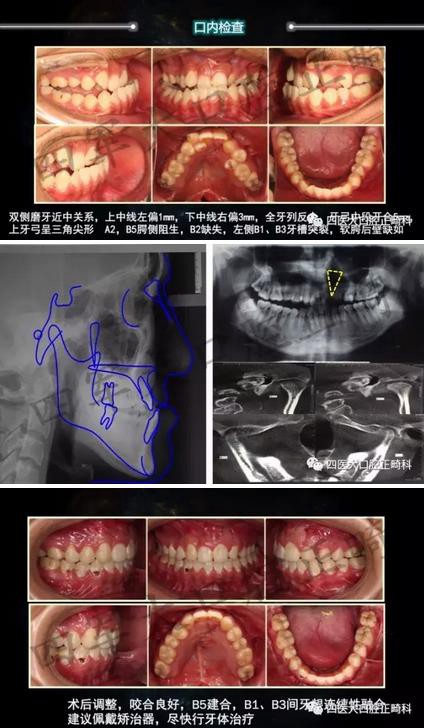

在剛剛閉幕的“絲綢之路口腔正畸學(xué)術(shù)年會暨疑難錯合畸形多學(xué)科綜合診治研討會”上,我們隆重舉辦了一年一度的四醫(yī)大口腔正畸科青年醫(yī)師病例展示,各路新俊都大顯身手。小編會分五輯為您呈現(xiàn)每位青年醫(yī)生的精彩病例片段,歡迎各位患者及同行朋友圍觀

矯牙選擇恐懼癥?不怕!

來源:四醫(yī)大口腔正畸科